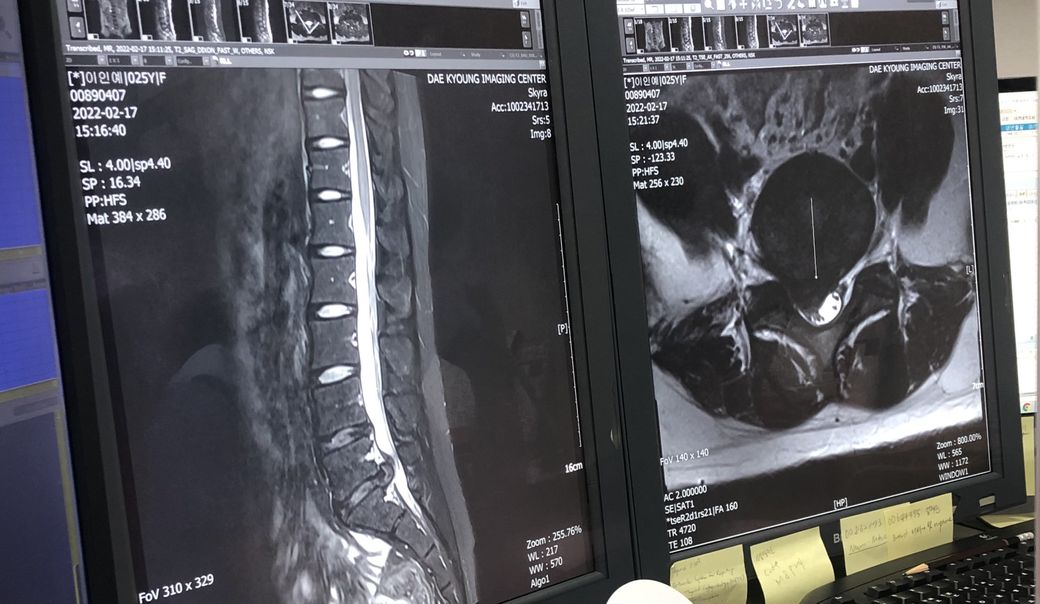

허리디스크 수술 해야할까요?보존치료도가능할까요?

27살 여자구요 주로 앉아서 일하고 고개와 허리를 굽혀 일합니다. 약 한달전부터 허리가아팟고 동네 정형외과애서 엑스레이를찍고 mri권유를 해서 더큰 정형외과로 갔습니다 .그병원에서도 엑스레이를 먼저찍었는데 아직 젊어서 괜찮을거라 하시며 영상판독은 나중에 하자며 약복용과 물리치료(골반견인) 해왔습니다. 그때부터 다리저림(절뚝거림) 과 엉치뼈쪽 고통과 앉을때와 서있을때도 고통이있어 결국 다니던 정형외과와 제휴?를 맺은 곳에서 영상을찍었는데 그 곳 의사분은 시술이나 수술을 고려해봐야할 정도라고 하셨고 영상씨디를 다시가지고와 정형외과에서 꼬리뼈주사(신경차단) 을맞고 수술이나 시술은 보류해보자면서 몇일이지났는데도 통증은 여전해 다시 병원을 갔는데 지금도 약이 쎈거라 하시면서 진통제를 더 처방해주셨는데 고통은 살짝 줄었지만 욱씬하고 얼얼한느낌은 계속납니다. 제가 꼭 수술이나 시술을 해야하는지 궁금하고 제증상이 심한건지 알고싶습니다.

허리 MRI자체만을 보자면 현재 디스크의 탈출 정도는 심한편입니다.

• MRI 소견을 통해 보았을 때에 질문자님의 디스크 상태는 매우 심한 편으로 보입니다. 하지만 그와는 별개로 하지의 근력 저하나 감각 저하와 같은 신경학적 소견 없이 통증만 있는 상태라면 시술 보다는 코어 근육 강화, 체중 감소 등을 통해서 척추에 가해지는 부담 자체를 줄여 디스크의 호전을 기대해보시는 것이 근본적인 해결법입니다. 시술을 받으면 당장은 어느 정도 호전될 수 있지만 다시 디스크가 악화될 우려가 높습니다.